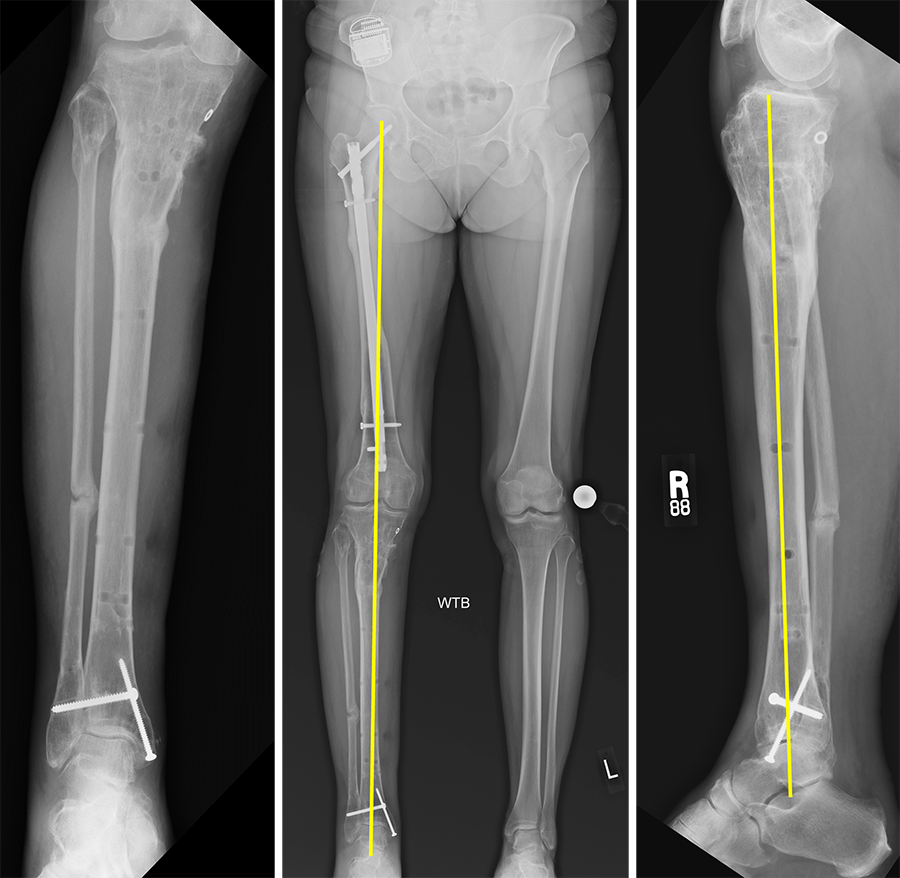

(Case provided by J. Spence Reid, Penn State Health Milton S. Hershey Medical Center, Pennsylvania, USA.)

- 47-year-old woman s/p separate femur and tibia trauma

- Valgus knee with external rotation through femur

- Deformity analysis revealed that the angular deformity was coming from her proximal tibia.

The treatment plan was to remove the femoral intramedullary (IM) nail, to perform a derotational osteotomy of the femur with an internal saw, and then to refix the femur with a new antegrade IM nail.

The tibial deformity was planned to be managed with a MAXFRAME AUTOSTRUT™.